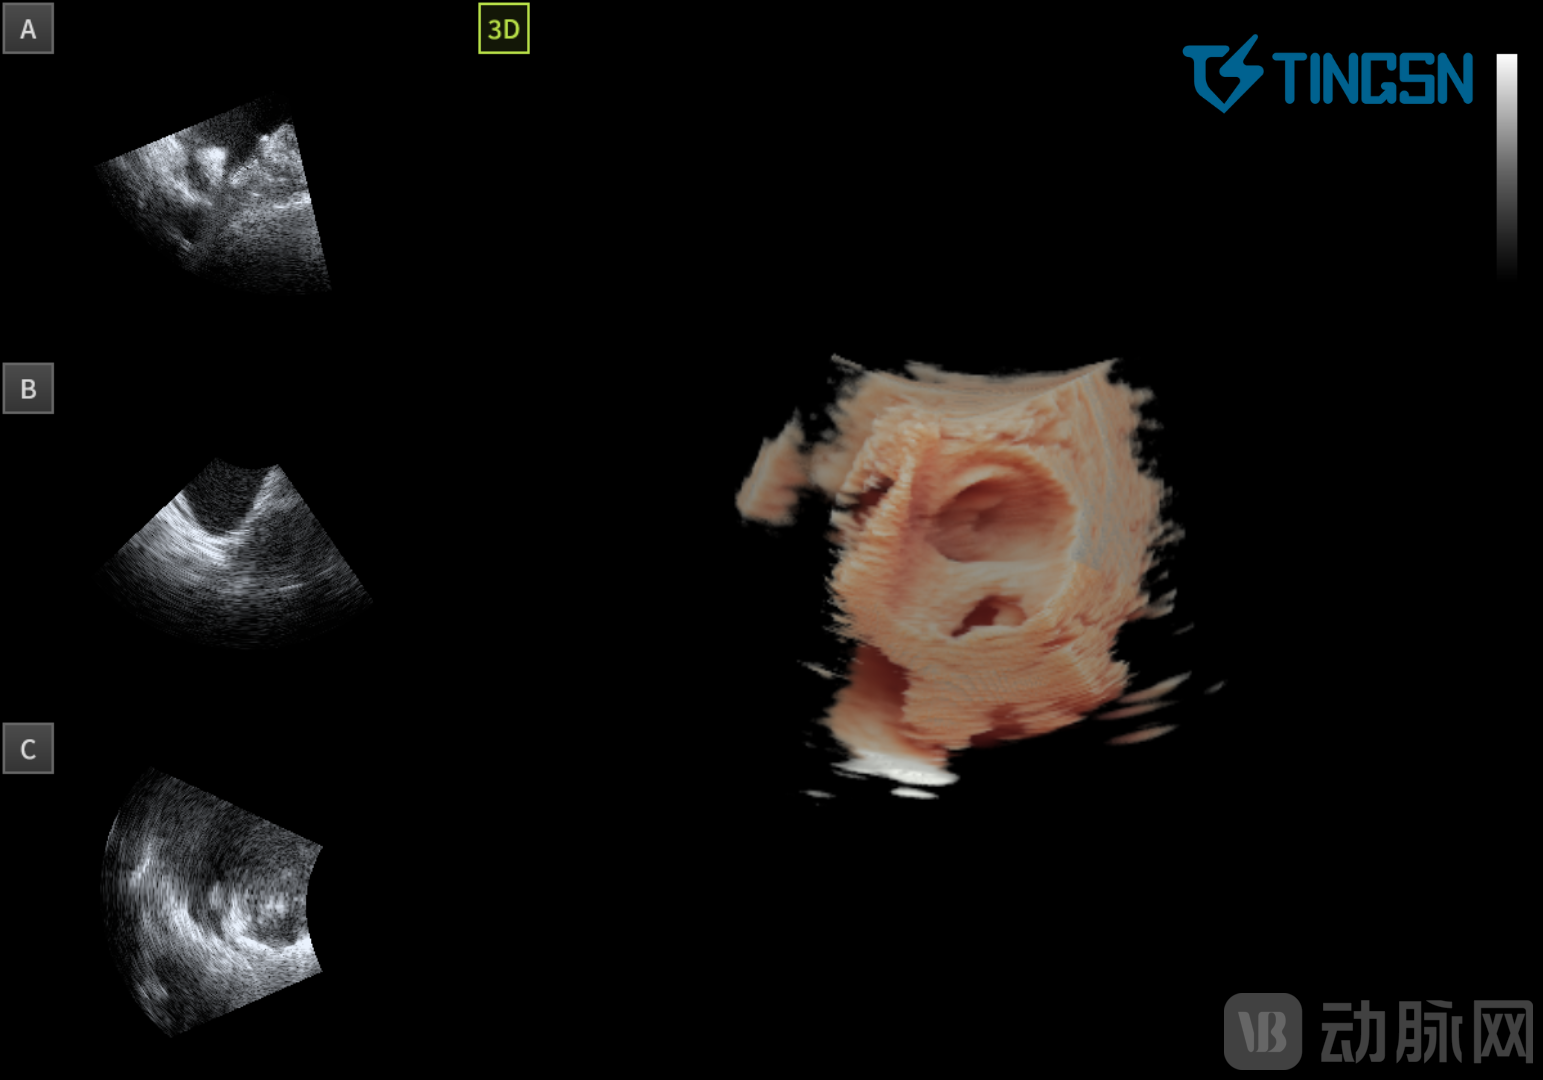

04 二尖瓣